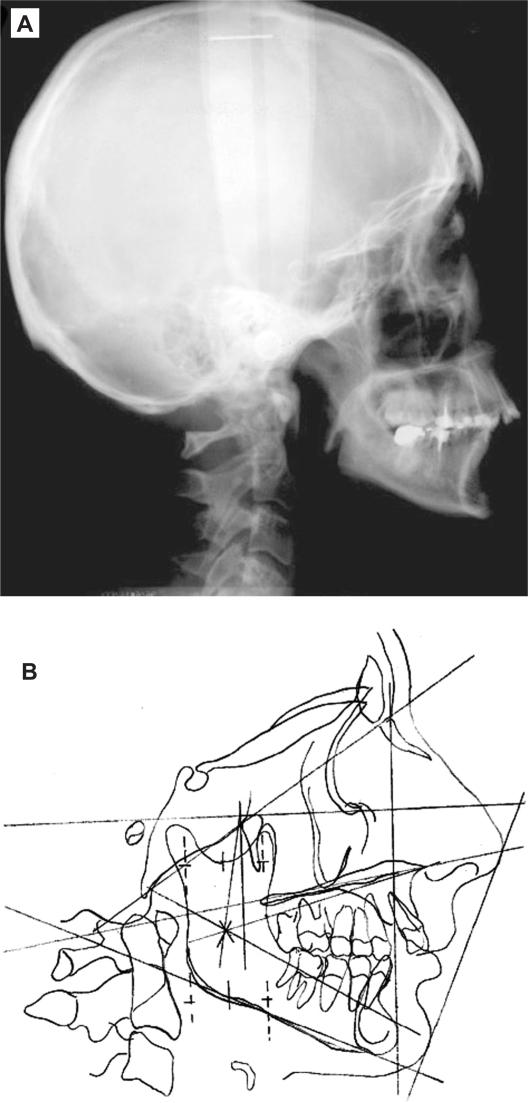

We describe the long-term complications six years after chemoradiotherapy in a 20-year old woman with nasopharyngeal carcinoma. We wanted to know whether the radiation dose was constant throughout the oral cavity, and thus uniformly affecting the corresponding dental and skeletal structures. Clinical and radiologic findings are described six years after chemoradiotherapy based on a two-dimensional computerized treatment planning system. This revealed radiation caries limited only to posterior teeth, proximal caries in the anterior teeth, limited but continuous salivary flow, mild periodontal infection, mild xerostomia, and a regenerative capacity of bones and the developmental process. The quantitative assessment of radiation delivered to the mandible revealed a high radiation dose in the posterior area and a minimal dose in the anterior area. This explains the differences in caries manifestation between the anterior and posterior teeth. According to the present study, individualized radiation fields, using a two-dimensional treatment planning system, result in restriction of severe damage of the dental and skeletal structures, which usually follows chemoradiotherapy. Orthodontic treatment could be initiated according to individual patient needs.

我们描述了一位 20 岁女性鼻咽癌患者在接受放化疗 6 年后的长期并发症。我们想知道口腔内的辐射剂量是否保持恒定,从而均匀地影响相应的牙齿和骨骼结构。根据二维计算机治疗计划系统,在放化疗 6 年后描述了临床和影像学发现。结果显示,放射性龋齿仅限于后牙,前牙邻面龋,唾液流量有限但连续,轻度牙周感染,轻度口干,以及骨骼和发育过程的再生能力。对下颌骨接受的辐射剂量进行定量评估,发现后牙区的辐射剂量较高,前牙区的辐射剂量较低。这解释了前牙和后牙龋齿表现的差异。根据本研究,使用二维治疗计划系统的个体化放射野可限制通常由放化疗引起的牙齿和骨骼结构的严重损伤。可根据患者个体需求启动正畸治疗。